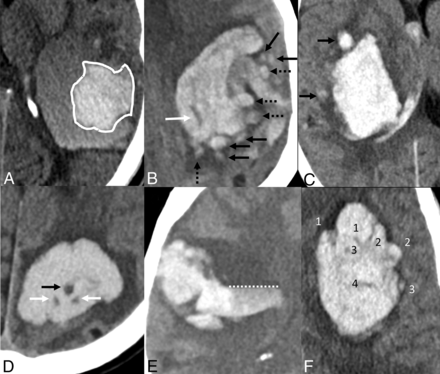

The spot sign is among the most studied imaging-based predictors of HE.3,8 However, a CTA is not routinely available in the acute setting. The spot sign only mildly improves predictive accuracy when added to other established predictors of HE.8⇓-10 Multiple NCCT hematoma expansion markers (EMs) have been recently developed (Fig 1) in an attempt to mitigate those limitations.4 These EMs may reflect the cascade phenomenon that occurs during HE, in which secondary hemorrhagic foci lead to irregular margins and heterogeneous density. They are classified as shape (Barras shape, island, and satellite) and density markers (Barras density, black hole, blend, fluid level, hypodensity, and swirl). EMs are associated with sHE, with ORs ranging from 2.01 to 7.87.11 These markers may be integrated into prediction models to select patients at higher risk of HE for more intensive monitoring and/or treatment or trials in acute ICH.12,13 They could also be used when other predictors of HE are not available, such as time in unknown-onset ICH.14

NCCT hematoma EMs. A, Blend sign: a relatively hypoattenuating area next to a hyperattenuating area of the hematoma, with a well-defined margin and a density difference of >18 HU between the 2 areas. B, Island sign: at least 3 scattered small hematomas all separate from the main hematoma (black arrows) or at least 4 small hematomas, some or all of which may connect with the main hematoma (dashed arrows), all visible on a single axial section. The white arrow identifies both a hypodensity (any hypodense region strictly encapsulated within the hemorrhage with any shape, size, and density) and a swirl sign (rounded, streak-like, or irregular region of hypo- or isoattenuation compared with the brain parenchyma that does not have to be encapsulated in the hematoma). C, Satellite sign: a small hematoma (diameter of <10 mm) separate from the main hemorrhage in at least 1 section and distinct from the main hematoma by a 1- to 20- mm separation (black arrows). D, Black hole sign: a hypoattenuating area with a density difference of >28 HU compared with the surrounding hematoma, which has no connection with the surface outside the hematoma (black arrow). This finding also corresponds to a hypodensity and a swirl sign. For the 2 hypodense foci labeled with white arrows, because the density difference with the hyperattenuating hematoma is <28 HU, they cannot be considered black hole signs. E, Fluid level: presence of 1 distinct hypoattenuating area (hypodense to the brain) above 1 hyperattenuating area (hyperdense to the brain), below a discrete straight line of separation (dashed line), irrespective of its density appearance. F, Barras density and shape signs are evaluated on the axial section showing the largest hematoma area and are based on a 5-point scale. Density is considered heterogeneous when there are ≥3 hypodensity foci within the hyperdense hematoma (scale of III, IV, or V). Shape is considered irregular when there are ≥2 focal hematoma margin irregularities, joined or separate from the hematoma edge (scale of III, IV, or V). Definitions from Morotti et al.4